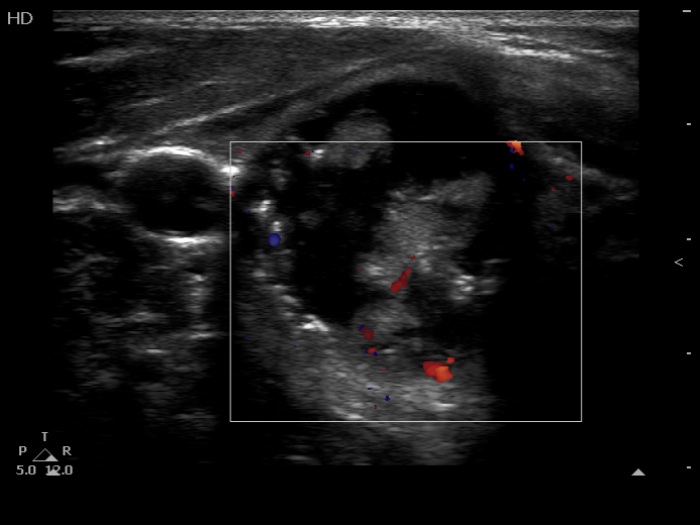

The composition of the nodule - case 1511 (ultrasonographic picture 7)

Right lobe, transverse scan, color Doppler mode. The vascularization is not specific.